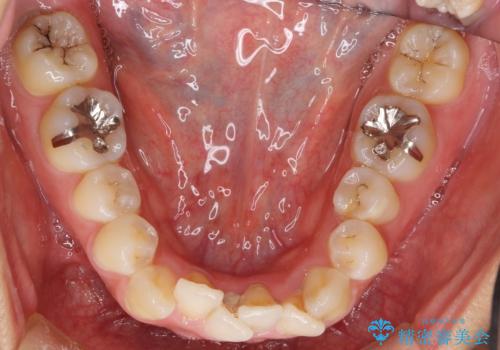

- 矯正装置

- ワイヤー矯正

- 前歯のがたつきを主訴に来院。

前歯のクロスバイト、上の前歯の正中が右にずれていました。

上下左右の小臼歯を抜歯しています。